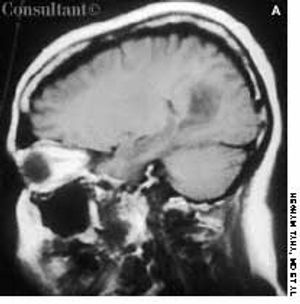

Headache and vomiting suddenly developed in a 41-year-old woman who was 16 weeks pregnant. The next day, she suffered an episode of tonic-clonic seizures associated with a 15-minute loss of consciousness.